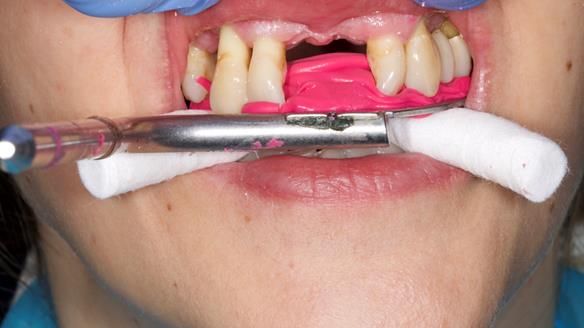

She had previously suffered from generalised periodontitis – stage IV, grade C, currently stable, with reduced attachment across the upper arch.

By the time she came to me, her periodontal condition was stable — but the aesthetics in the upper jaw were very poor.

Dr Syed Abad — my colleague and a Specialist in Periodontics — had successfully stabilised her gum health.

Syed also places implants at our practice, so Adnana was fully informed of all possible options.

We provided her with an immediate upper denture (Mk 1), followed by a definitive metal-based upper denture (Mk 2). A lower removable partial denture was discussed, to be made only if needed once the upper treatment was complete. However, at review, this wasn’t necessary — Adnana had excellent neuromuscular control and function, even with a shortened dental arch (SDA).